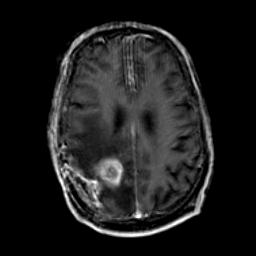

Glioma Overlay -- Slice #14

[Home][Help][Clinical] Slice 14